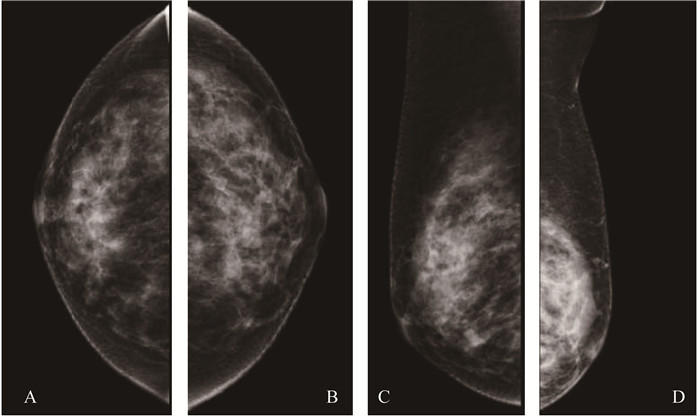

患者乳腺钼靶图像